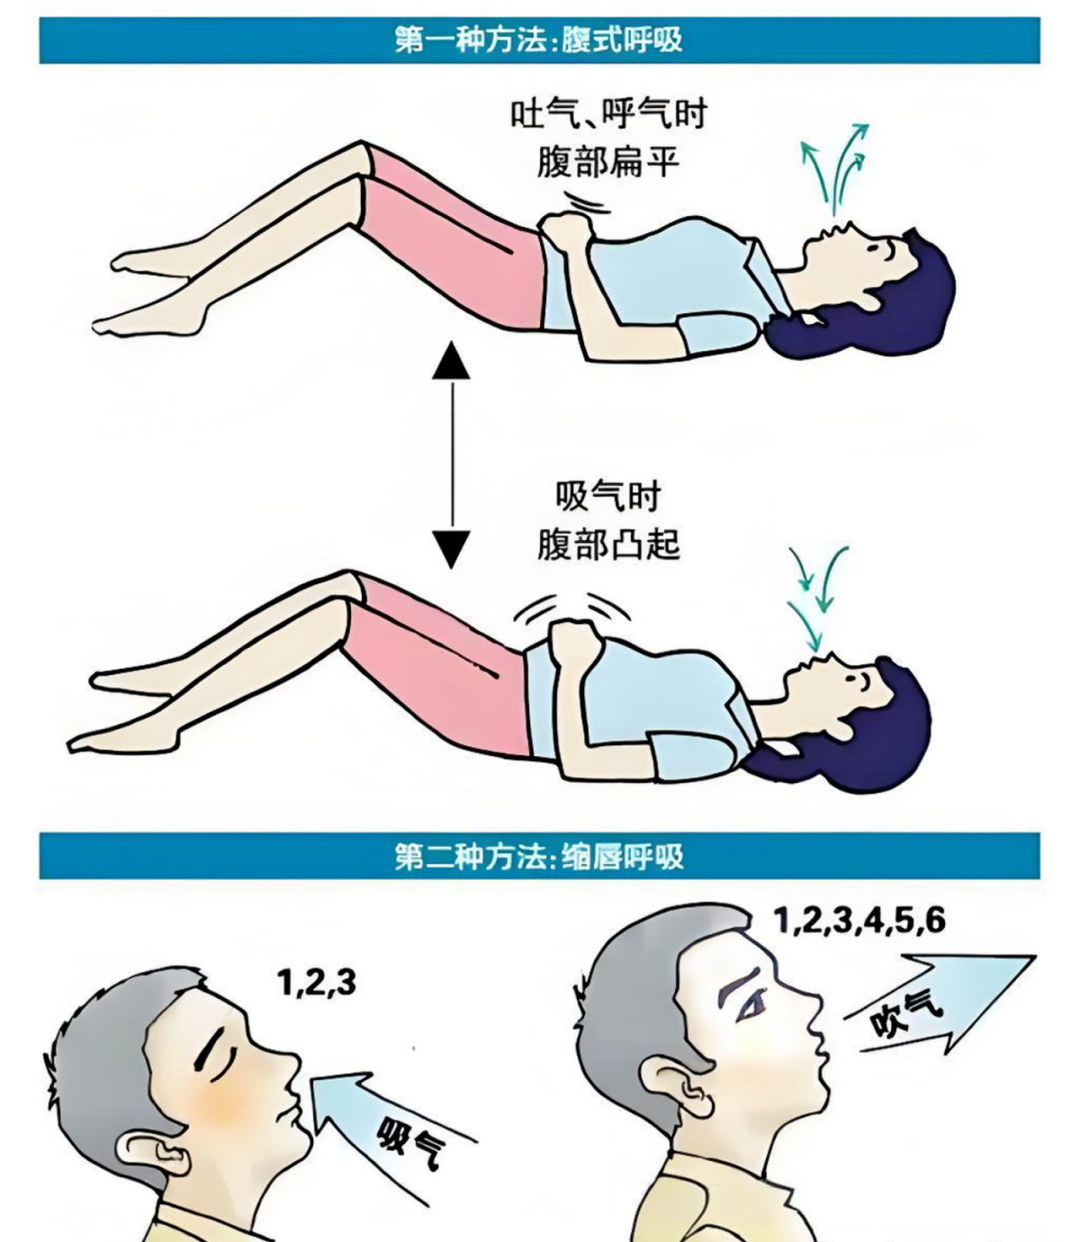

4.呼吸训练防肺部感染:尤其是老年患者,要多做深呼吸练习,比如腹式呼吸(吸气时腹部凸起,呼气时腹部扁平)、缩唇呼吸(吸气数3秒,呼气数6秒),预防肺部感染。